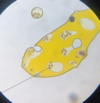

AVIAN COCCIDIA

Schizonts full of

trophozoites or merozoites

AVIAN COCCIDIA

Schizonts full of trophozoites or merozoites

AVIAN COCCIDIA

Schizonts full of trophozoites or merozoites